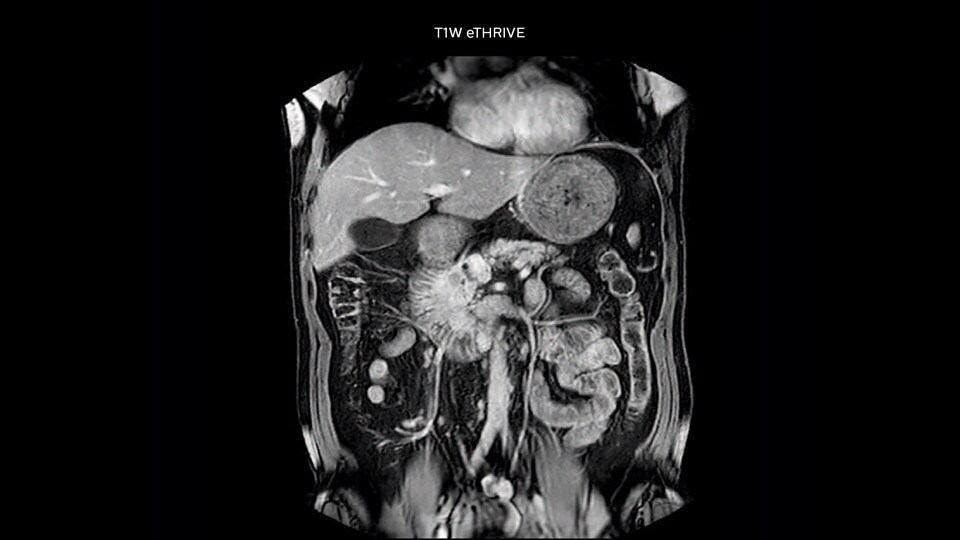

“Our liver exams are quite fast,” says Dr. Baumann. “If the patient tolerates it, we use an arms-up position to reduce the FOV and speed up the exam with dS SENSE.” “We acquire one transversal high resolution T2-weighted sequence with 3 mm slice thickness, for example for pancreas or liver lesions. Then we also add a T2 fat suppressed MultiVane XD SPIR sequence. We perform these two routinely in our liver imaging. We use high dS SENSE factors to significantly shorten scan times to 2-4 minutes, which can improve our protocol; it’s a very robust scan.” “We include mDIXON for the dynamic sequences because of the robust and homogeneous fat suppression we get with that. We had been using eTHRIVE, but we are now quite happy with mDIXON. Sometimes we use a medication to calm the bowels, to further improve the image quality.”